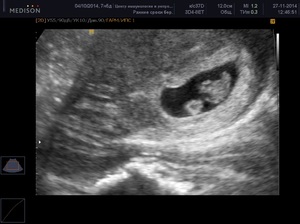

- Пройти УЗИ, которое дает 100% точный результат. Это исследование выполняется после консультации с гинекологом и постановки на учет. УЗИ не только подтверждает наличие беременности, но и помогает определить ее срок, а также выявить возможные патологии в развитии эмбриона.